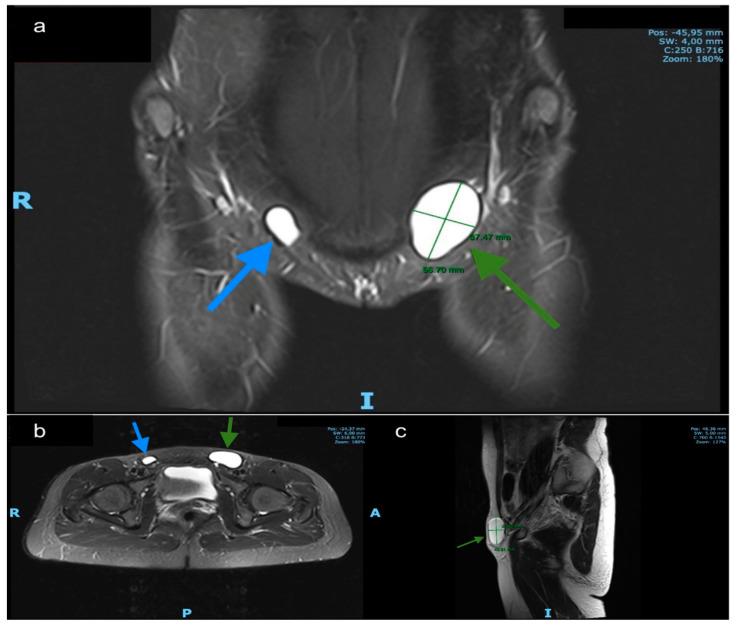

Nuck's hydroceles, which develop in a protruding part of the parietal peritoneum into the female inguinal canal, are rare abnormalities and a cause of inguinal swelling, mostly resulting in pain. They appear when this evagination of the parietal peritoneum into the inguinal canal fails to obliterate. Our review of the literature on this topic included several case reports and two case series that presented cases of Nuck hydroceles which underwent surgical therapy. We present six consecutive cases of symptomatic hydroceles of Nuck's canal from September 2016 to January 2020 at the Department of Surgery of Charité Berlin. Several of these patients had a long history of pain and consecutive consultations to outpatient clinics without diagnosis. These patients underwent laparoscopic or conventional excision and if needed simultaneous hernioplasty in our institution. Ultrasonography and/or Magnetic Resonance Imaging were used to display the cystic lesion in the inguinal area, providing the diagnosis of Nuck's hydrocele. This finding was confirmed intraoperatively and by histopathological review. Ultrasound and magnetic resonance imaging (MRI) captures, intraoperative pictures and video of minimal invasive treatment are provided. Nuck's hydroceles should be included in the differential diagnosis of an inguinal swelling. We recommend an open approach to external Type 1 Nuck´s hydroceles and a laparoscopic approach to intra-abdominal Type 2 Nuck hydroceles. Complex hydroceles like Type 3 have to be evaluated individually, as they are challenging and the surgical outcome is dependent on the surgeon's skills. If inguinal channel has been widened by the presence of a Nuck's hydrocele, a mesh plasty, as performed in hernia surgery, should be considered.

努克水囊肿是在腹膜壁层向女性腹股沟管突出的部位形成的,是一种罕见的异常情况,也是腹股沟肿胀的一个原因,大多会导致疼痛。当腹膜壁层向腹股沟管的这种疝出未能闭塞时就会出现。我们对该主题的文献回顾包括几例病例报告和两个病例系列,这些病例系列展示了接受手术治疗的努克水囊肿病例。我们呈现了2016年9月至2020年1月在柏林夏里特医院外科连续收治的6例有症状的努克管水囊肿病例。这些患者中有几位有长期疼痛病史,并连续在门诊就诊但未得到诊断。这些患者在我们机构接受了腹腔镜或传统切除术,必要时同时进行疝修补术。使用超声和/或磁共振成像来显示腹股沟区的囊性病变,以诊断努克水囊肿。这一发现通过术中及组织病理学检查得以证实。文中提供了超声和磁共振成像(MRI)图像、术中照片以及微创治疗的视频。努克水囊肿应列入腹股沟肿胀的鉴别诊断范围。对于外部1型努克水囊肿,我们建议采用开放手术方法;对于腹腔内2型努克水囊肿,建议采用腹腔镜手术方法。像3型这样的复杂水囊肿必须单独评估,因为它们具有挑战性,手术结果取决于外科医生的技能。如果腹股沟管因努克水囊肿的存在而变宽,应考虑像疝手术那样进行补片修补术。